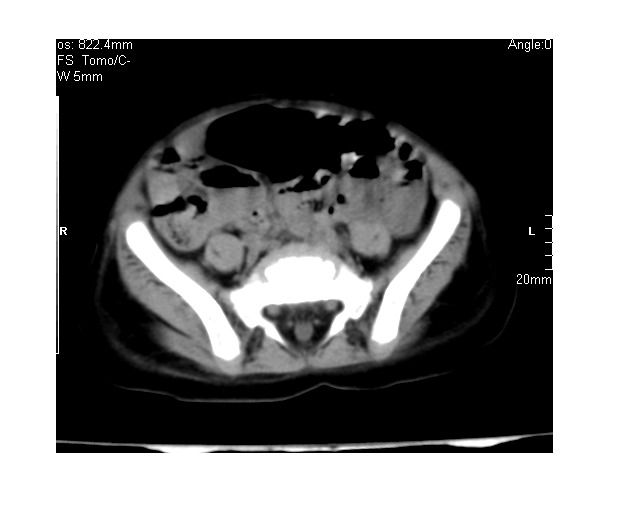

以下是引用lkc8963在2008-3-16 12:49:00的发言:[br]盆底巨大混杂密度肿块,富含多种组织成分包括脂肪/液体/软组织/钙化,边界清楚,向前压迫肠管及膀胱,向后突入骶尾部皮下脂肪层,首先考虑畸胎瘤,诊断时需要与脊柱裂/囊性淋巴管瘤等区别。